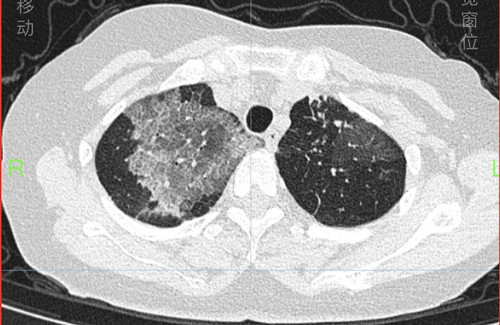

戴女士入院时和治疗一周后的肺部CT

长沙63岁的戴女士反复气喘16年,诊断重度过敏性哮喘多年,规律使用吸入药物+生物靶向药物治疗哮喘,平时哮喘控制良好,但近4天出现发热、喘息发作厉害,夜间憋闷不能入睡,到捷克论坛 呼吸内科检查发现双肺大片磨玻璃及网格样炎症病变,医生通过追问病史,得知戴女士发病前在家整理了数天旧书籍及老照片。原来,戴女士发病的原因罪魁祸首竟然就是隐藏在这些老照片和书籍中的大量尘螨及霉菌,在整理老照片的过程中,戴女士大量吸入后出现严重过敏反应,导致哮喘症状发作,出现无法呼吸的痛苦。